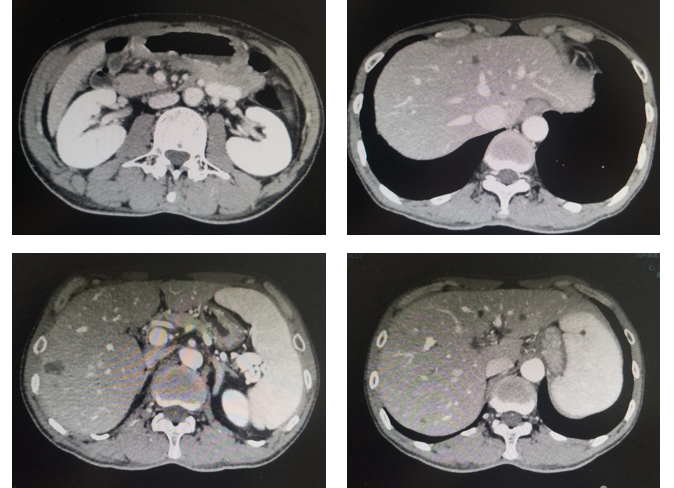

治疗:现给与卡培他滨+曲妥珠单抗+PD-1单抗维持治疗3周期,末次复查CT见图4,血肿瘤标志物AFP水平变化(图5)。

图5. 腹部CT平扫+强化(治疗后7月,2020年5月)

内科:根据影像学判效PR,复查CT确认PR,提示目前治疗方案有效,但患者应用7周期治疗后出现I度末梢神经毒性和奥沙利铂过敏,因此建议停用奥沙利铂改为卡培他滨+曲妥珠单抗+PD-1单抗维持治疗。

影像科:根据患者治疗前、治疗后首次及再次复查CT看,原发病灶胃壁增厚明显减轻,肝转移病灶明显缩小,部分病灶消失,首次CT判效PR,再次复查CT确认PR。提示内科治疗有效。

MDT汇总意见:目前经7周期XELOX+曲妥珠单抗+PD-1单抗治疗有效,复查CT确认PR,治疗过程中未出现梗阻、出血及穿孔等需要外科干预的情况,因此继续内科治疗为主,化疗出现奥沙利铂的Ⅰ度末梢神经毒性和过敏,因此下阶段建议停用奥沙利铂进入维持治疗。